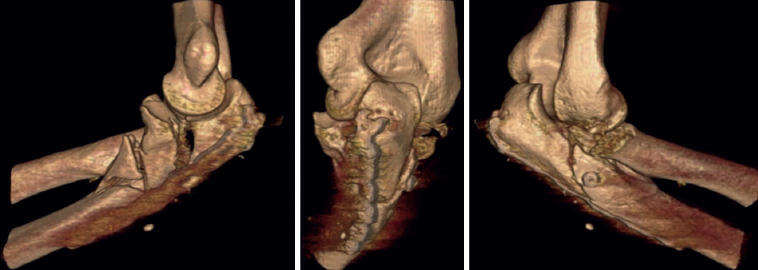

A pesar de que no existe un consenso en relación con la clasificación de las fracturas-luxaciones del codo y ateniéndonos al concepto fractura-luxación transolecraneana, en estas lesiones debe existir una fractura intraarticular del olécranon, con solución de continuidad en la cortical posterior del cúbito, en la que se ve comprometida la estabilidad humerocubital. Si no existe una luxación de la articulación radiocubital proximal, el término adecuado es “fractura-luxación transolecraneana” y, si se asocia una luxación de la articulación radiocubital proximal, “fractura-luxación variante de Monteggia” (Figura 1). Los estudios radiológicos no siempre permiten diferenciar claramente los patrones de fractura por lo que la tomografía axial computarizada (TAC) y especialmente las reconstrucciones tridimensionales son imprescindibles para su diagnóstico.

El desplazamiento del cúbito y del radio con respecto al húmero puede ser anterior o posterior tanto en la fractura-luxación transolecraneana como en la fractura-luxación variante de Monteggia (Figuras 2, 3 y 4). En los adultos, las fracturas-luxaciones transolecraneanas anteriores son menos frecuentes que las posteriores y se diferencian más fácilmente de las fracturas-luxaciones variante de Monteggia de tipo I que las fracturas-luxaciones transolecraneanas posteriores, que frecuentemente se confunden con fracturas-luxaciones variante de Monteggia de tipo II. En ambas lesiones existe una fractura intraarticular del olécranon, pueden asociar una fractura y/o luxación de la cabeza del radio y una fractura de la coronoides y, en las fracturas-luxaciones variante de Monteggia de tipo II, puede asociarse una lesión del ligamento colateral lateral(1,2,13,14,15).

Las fracturas transolecraneanas anteriores son consecuencia de un mecanismo de alta energía en el que la tróclea impacta con el olécranon mientras el codo está flexionado, produciendo un desplazamiento anterior del antebrazo con respecto al olécranon, que puede tener una fractura simple o con mayor frecuencia ser conminuta(14). No hay lesión de la articulación radiocubital proximal, ni de la cabeza del radio ni de los ligamentos estabilizadores de la articulación humerocubital y la fractura de la coronoides es menos frecuente que en los casos con desplazamiento posterior. Las lesiones que mayor confusión suscitan son las fracturas-luxaciones transolecraneanas posteriores, que con frecuencia se confunden con las fracturas-luxaciones de Monteggia posteriores, donde el hecho diferenciador es la luxación de la articulación radiocubital proximal en estas últimas y su preservación en las primeras. El mecanismo lesional puede ser de baja energía (por ejemplo, caída de la persona desde su propia altura) en personas de edad avanzada, mayoritariamente mujeres con osteoporosis, o de alta energía (caídas desde grandes alturas o accidentes de tráfico) en jóvenes, que asocian politraumatismo y fracturas abiertas. Las fracturas y/o luxaciones de la cabeza del radio, las fracturas de la coronoides y la afectación de la porción cubital del ligamento colateral lateral son frecuentes en las fracturas-luxaciones transolecraneanas y las fracturas-luxaciones variante de Monteggia con desplazamiento posterior(1,2,13,14,15).